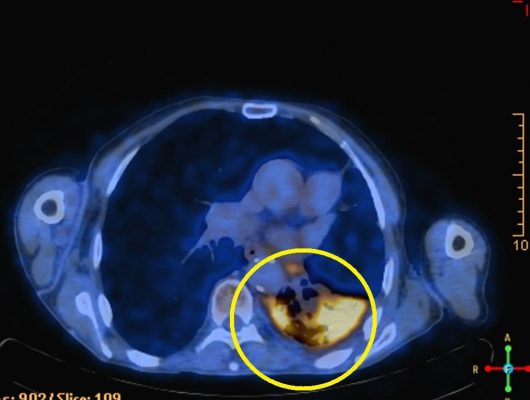

בבי"ח פוריה, בוצע לראשונה, ניתוח לכריתת ריאה, עם גידול סרטני ודלקת חסימתית

כריתת גידול בריאה ללא הרדמה

מטופלת עם מחלות רקע, נותחה באיכילוב ללא הרדמה כללית, כשהיא ערה ומתקשרת עם הצוות

כריתת גידול ריאתי, כשהמטופלת ערה

איכילוב: ניתוח לכריתת גידול בריאה ללא הרדמה כללית. המנותחת תקשרה עם הצוות המנתח